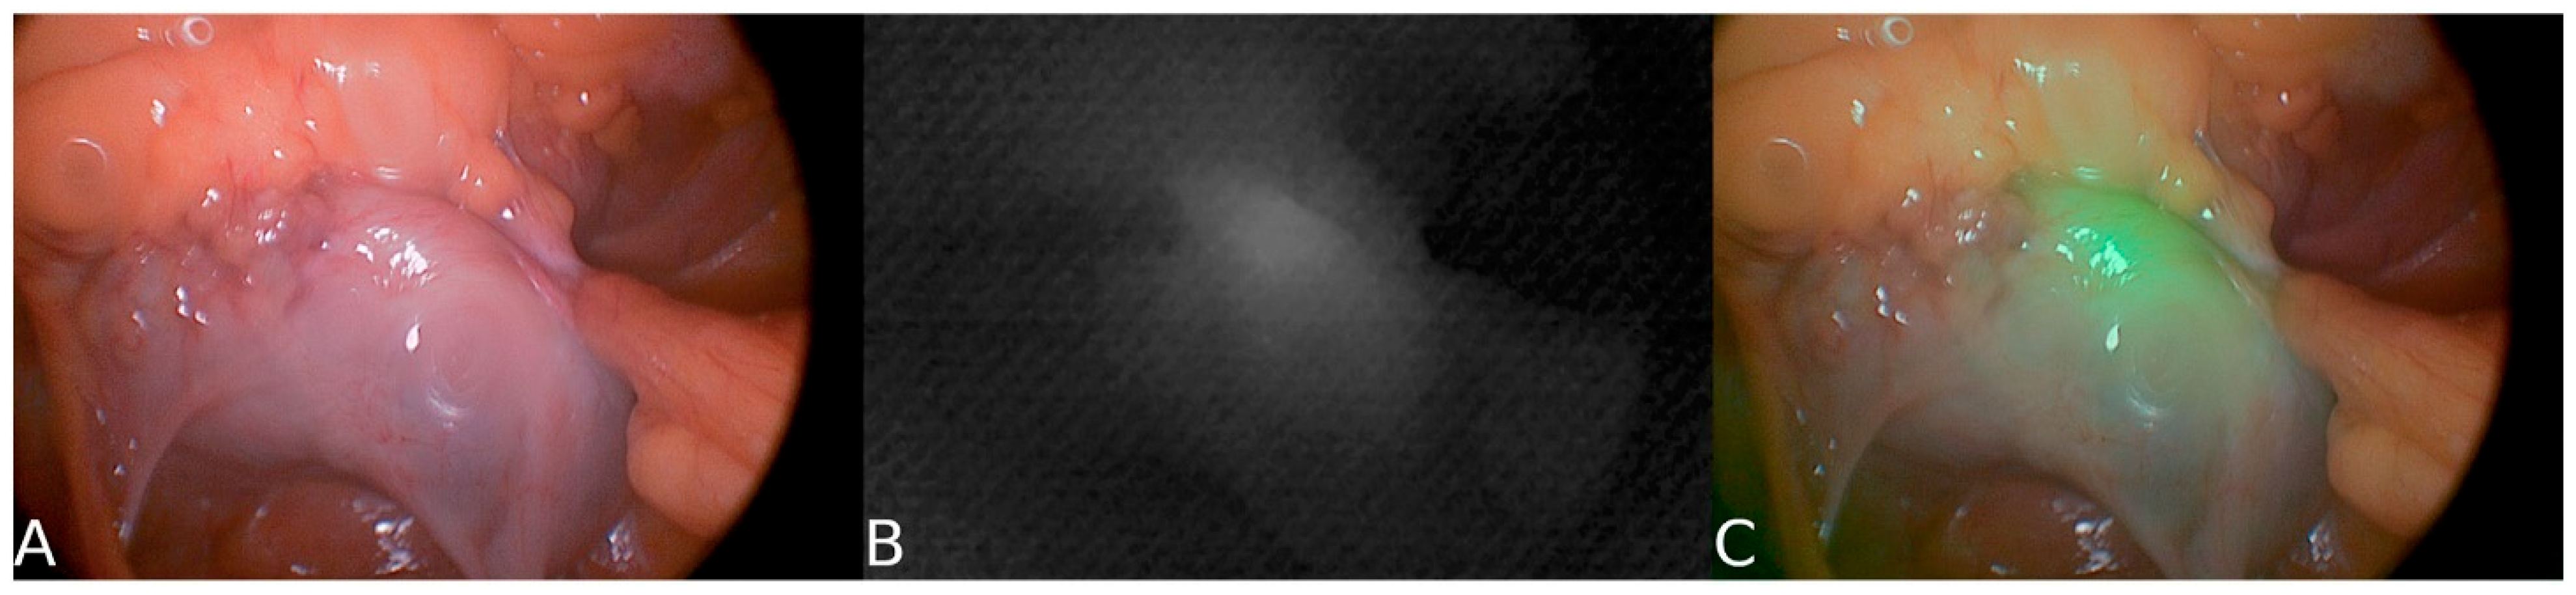

- Jin, H.; Zheng, L.; Lu, L.; Cui, M. Near-infrared intraoperative imaging of pelvic autonomic nerves: A pilot study. Surg. Endosc. 2022, 36, 2349–2356. [Google Scholar] [CrossRef] [PubMed]

| Hypogastric nerve (HGN) | ~93% | ~81% | Plexus-level visible | MRN has a higher POV; NIR aids in plexus contrast. | [37,41] |

| Pelvic plexus / IHP (PP) | ~65% | ~44% | SBR ≈ 3.18 | MRN > intraop POV; NIR improves real-time contrast. | [37,41] |

| Near-Infrared Fluorescence (NIR) | Uses ICG or targeted agents for real-time visualization | Improves intraoperative nerve visibility | [41,53] |